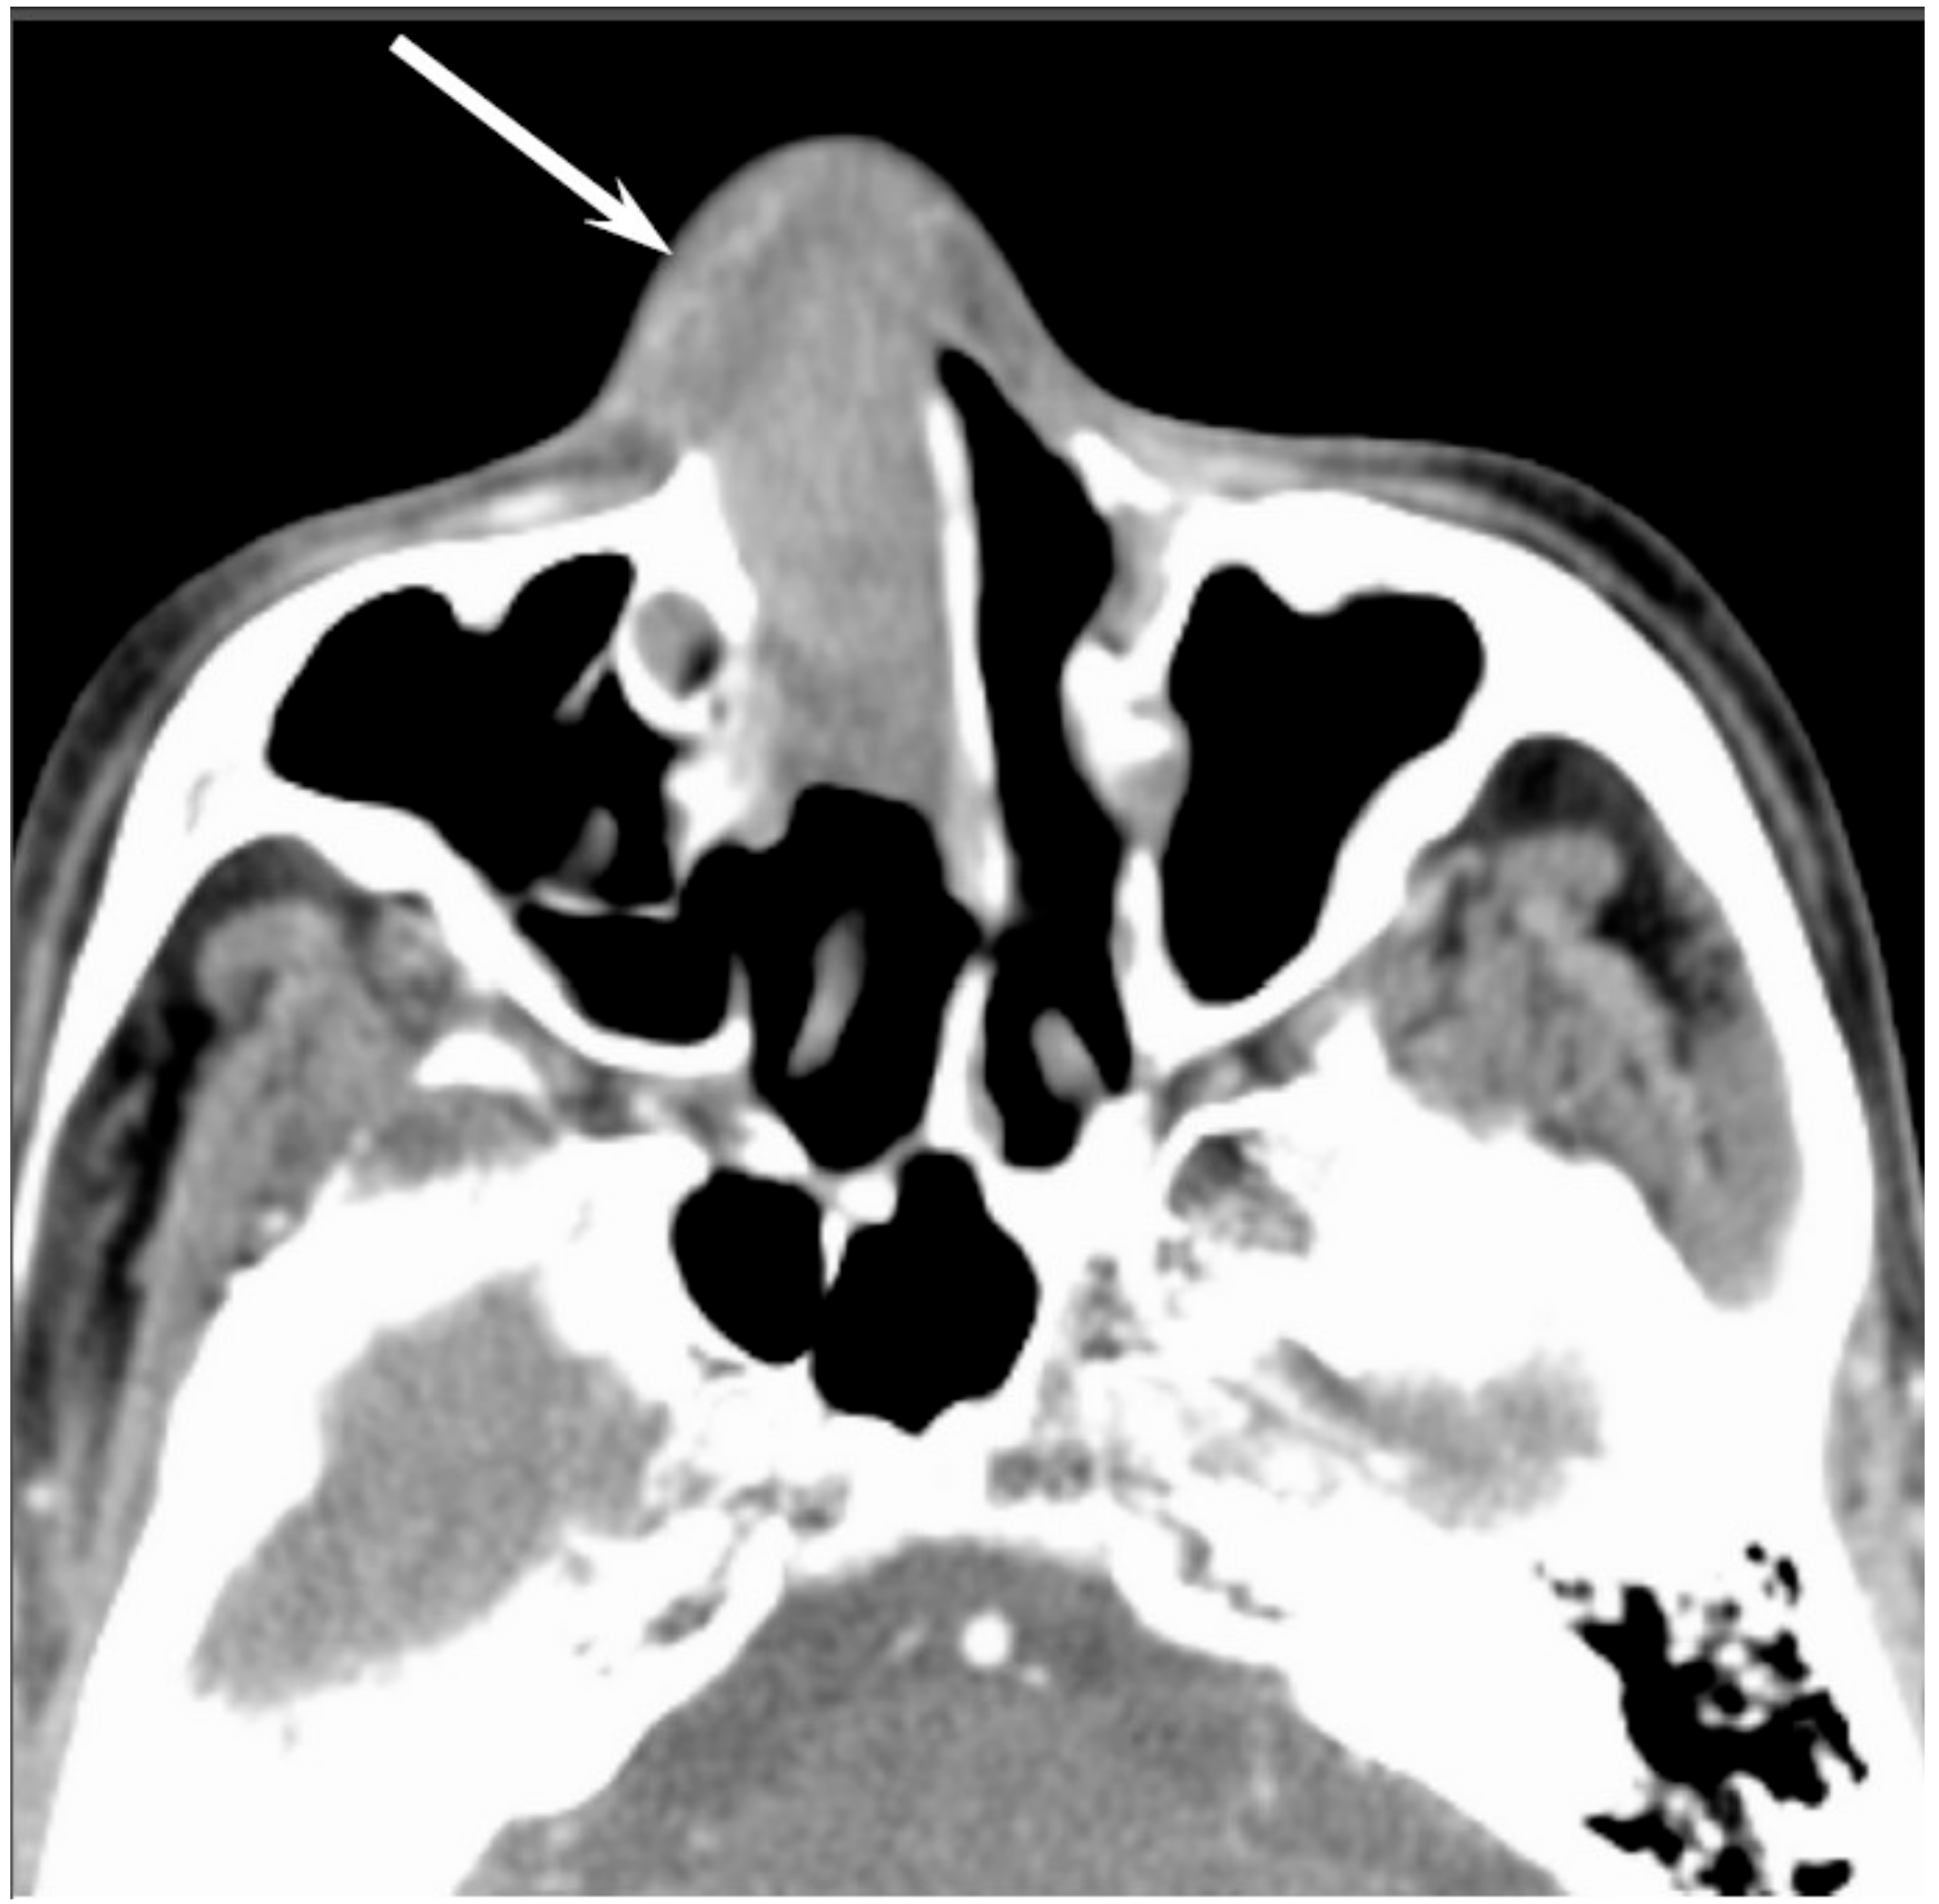

Figure 7. Olfactory neuroblastoma of the right nasal cavity. Contrast-enhanced CT image showing a homogeneously enhanced lesion in the right olfactory cleft (arrow).

On CT, ONBs appear as a homogeneous, well-defined soft-tissue mass. Scattered speckled calcifications may be observed within the tumor. The tumor commonly extends into the ethmoid and maxillary sinuses, but rarely involves the sphenoid sinus. CT is essential for the evaluation of osseous involvement of the cribriform plate, fovea ethmoidalis, and lamina papyracea. On MRI, ONBs usually show hypointensity relative to the gray matter on T1WI and hyperintensity relative to the gray matter on T2WI [33]. These tumors demonstrate an avid and homogeneous enhancement except for occasional areas of necrosis or hemorrhage (Figure 7). When an intracranial extension is present, the peripheral or marginal cysts are a characteristic and specific feature of ONBs [34].